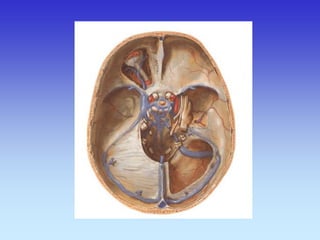

VASKULARNA OPSKRBA WILLIS-ijev prsten

a. cerebri ant.

a. cerebri media

a. cerebri post.